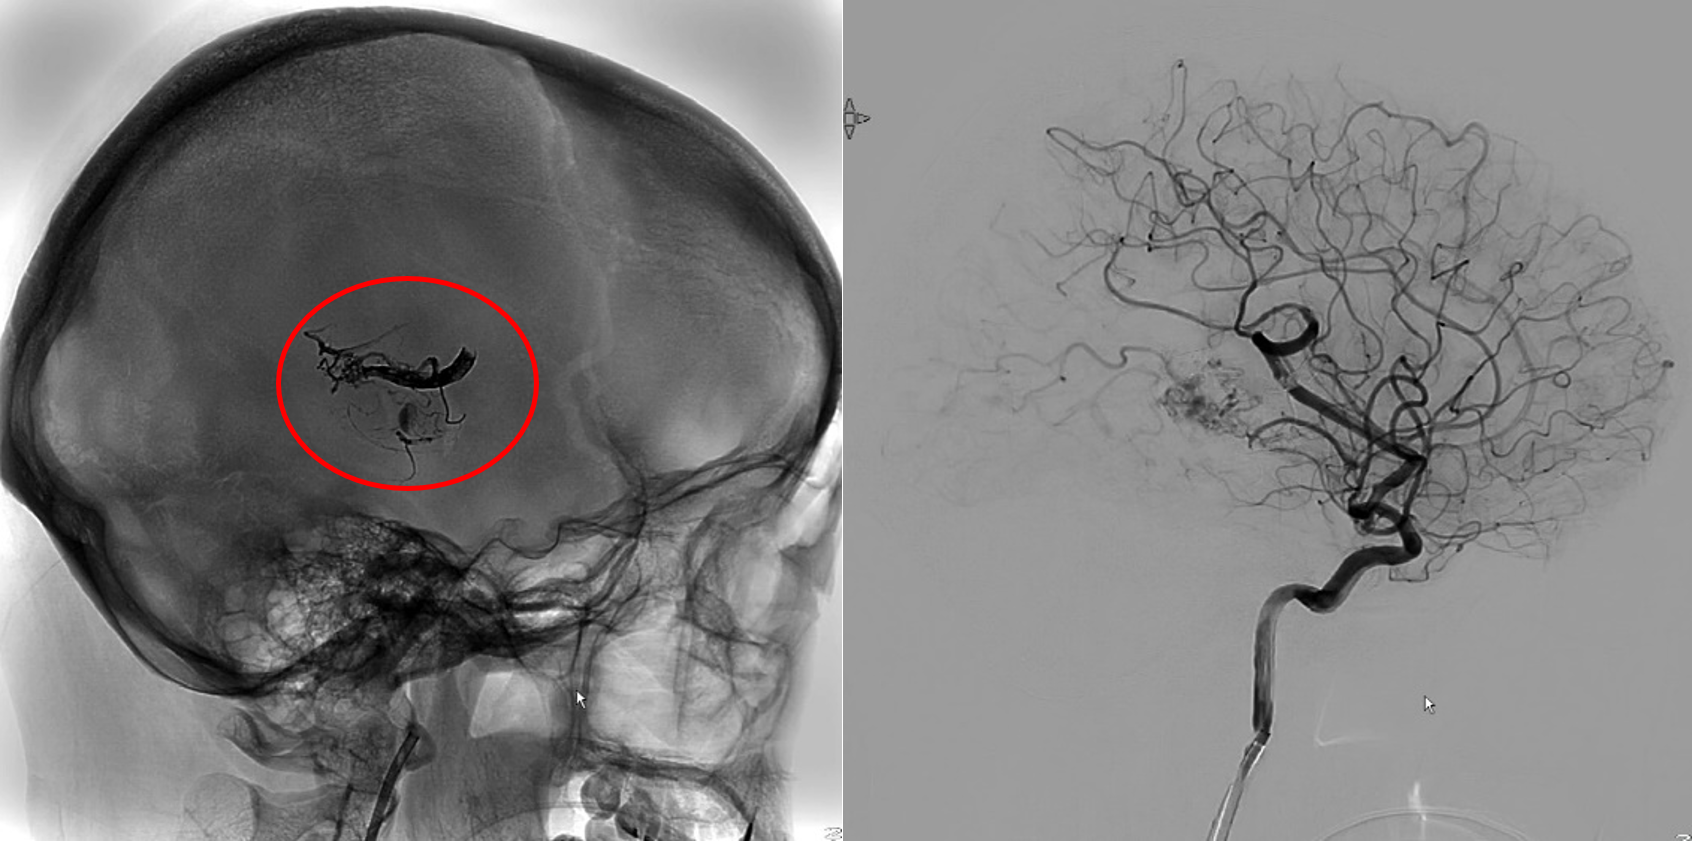

動静脈奇形がある場合、動脈は毛細血管を通さずに静脈と直接つながっているため、長時間動脈の血圧を支えることができず、静脈が破裂してしまいます。

この 2 つの間の異常な伝達はフィステルと呼ばれ、AVM 内に 1 つ以上存在する場合があります。

奇形動脈は太く拡張しており、血液循環が速いため、脳出血を起こすことがよくあります。

血液を排出する静脈も AVM プロセスによって拡張 (静脈瘤の出現) を受ける可能性があり、症例の 15% で動脈瘤が形成されます。どちらも脳出血を引き起こす可能性があります。

出血がある場合は、手術、塞栓術、および/または放射線手術で治療されます。症状が現れた場合は診察を受けてください。